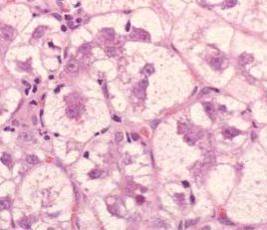

What is the type of necrosis demonstrated by these images?

Answer

• Liquefactive

• Fat

• Coagulative

• Caseous